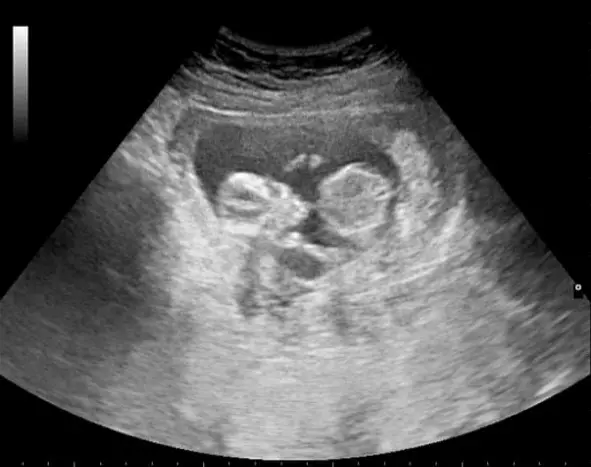

The appointment was quick. The staff performed a brisk ultrasound, flashed the image of the little baby at April, and told her what to expect after taking the drugs: period-like cramping and blood clots—perhaps the size of a lemon.

Now, two months later, April and her child—a boy due later this fall—continue to thrive.